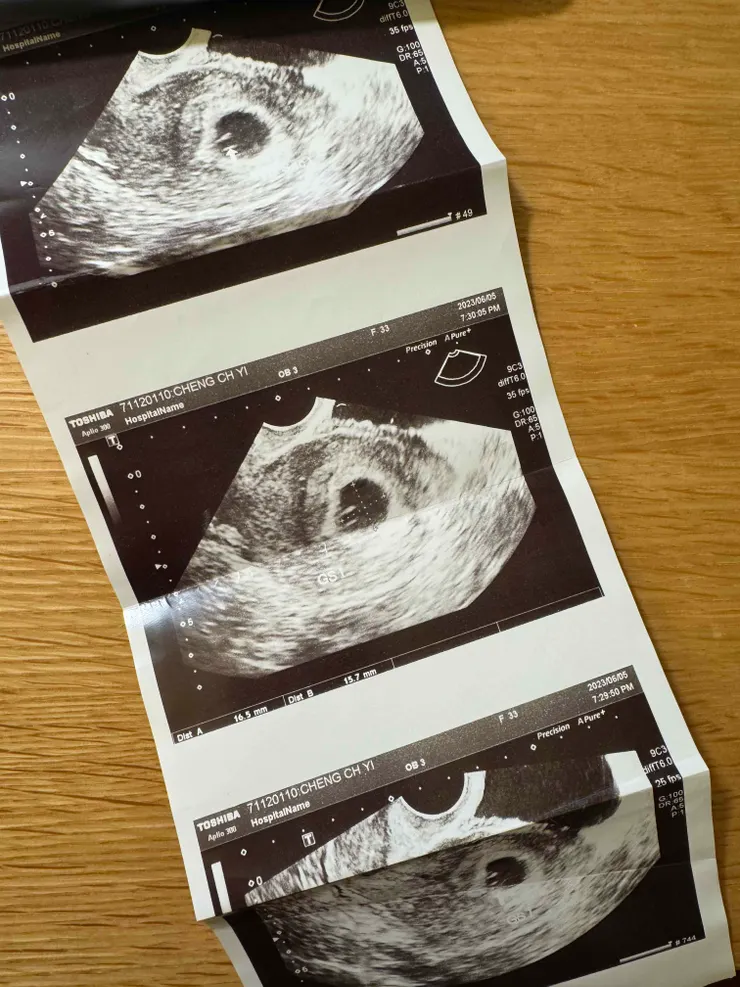

護理師給我看陰道超音波,說黑色的球球是妊娠囊(光是打這兩個字我都打不出來,還要去google搜尋「妊」然後「娠」跑出來再直接複製貼上!),我一臉疑惑,臨走前還再次問她到底那名稱是什麼。

醫生說兩個禮拜來看有沒有心跳,有的話就可以領媽媽手冊。蛤,我以為他會問我要不要?或是公式化地說聲恭喜,結果都沒有,一點drama都沒有(好,drama的是我自己)

還沒有心跳算懷孕嗎?他現在只是一個胚囊(我要用「他」了嗎?但現在還沒有生命吧?但我懶得選字算了)原來兩條線後有一堆事情要確認,他兩個禮拜後有沒有心跳都還不確定,那我現在又在什麼狀態?尚未準媽媽?